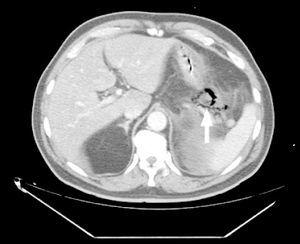

Paciente de 70 años sin antecedentes médicos de interés que acude al Servicio de Urgencias por un cuadro de dolor abdominal y vómitos. Se le diagnosticó pancreatitis aguda dado que la amilasemia era de 4.390 U/l. Ante la persistencia del dolor y la aparición de distensión abdominal se realizó una tomografía axial computarizada del abdomen que mostró signos de pancreatitis enfisematosa y colecistitis enfisematosa con cálculos (fig. 1). El paciente presentó deterioro del intercambio gaseoso, por lo que fue ingresado en la Unidad de Cuidados Intensivos. Tras consultar con el Servicio de Cirugía General se decidió la intervención quirúrgica urgente realizándose colecistectomía y apertura de la celda pancreática con drenaje de la cola, y se inició tratamiento sistémico con imipenem. Se llevó a cabo cultivo para aerobios y anaerobios del material obtenido a través de los drenajes y se observó crecimiento de Escherichia coli. El paciente evolucionó favorablemente y fue dado de alta a planta a los 23 días de su ingreso.

Figura 1.